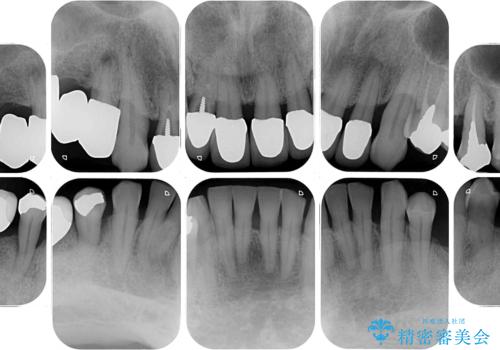

欠損部はインプラントによる補綴治療を行うこととし、臼歯部が安定した後に、上下前歯部をオールセラミッククラウンにて補綴治療を行うこととしました。

上顎前歯に歯周ポケットの深い部分がありましたが、インプラントの仮歯で奥歯がしっかりと噛めるようになると、1年程度で深い歯周ポケットは解消されました。